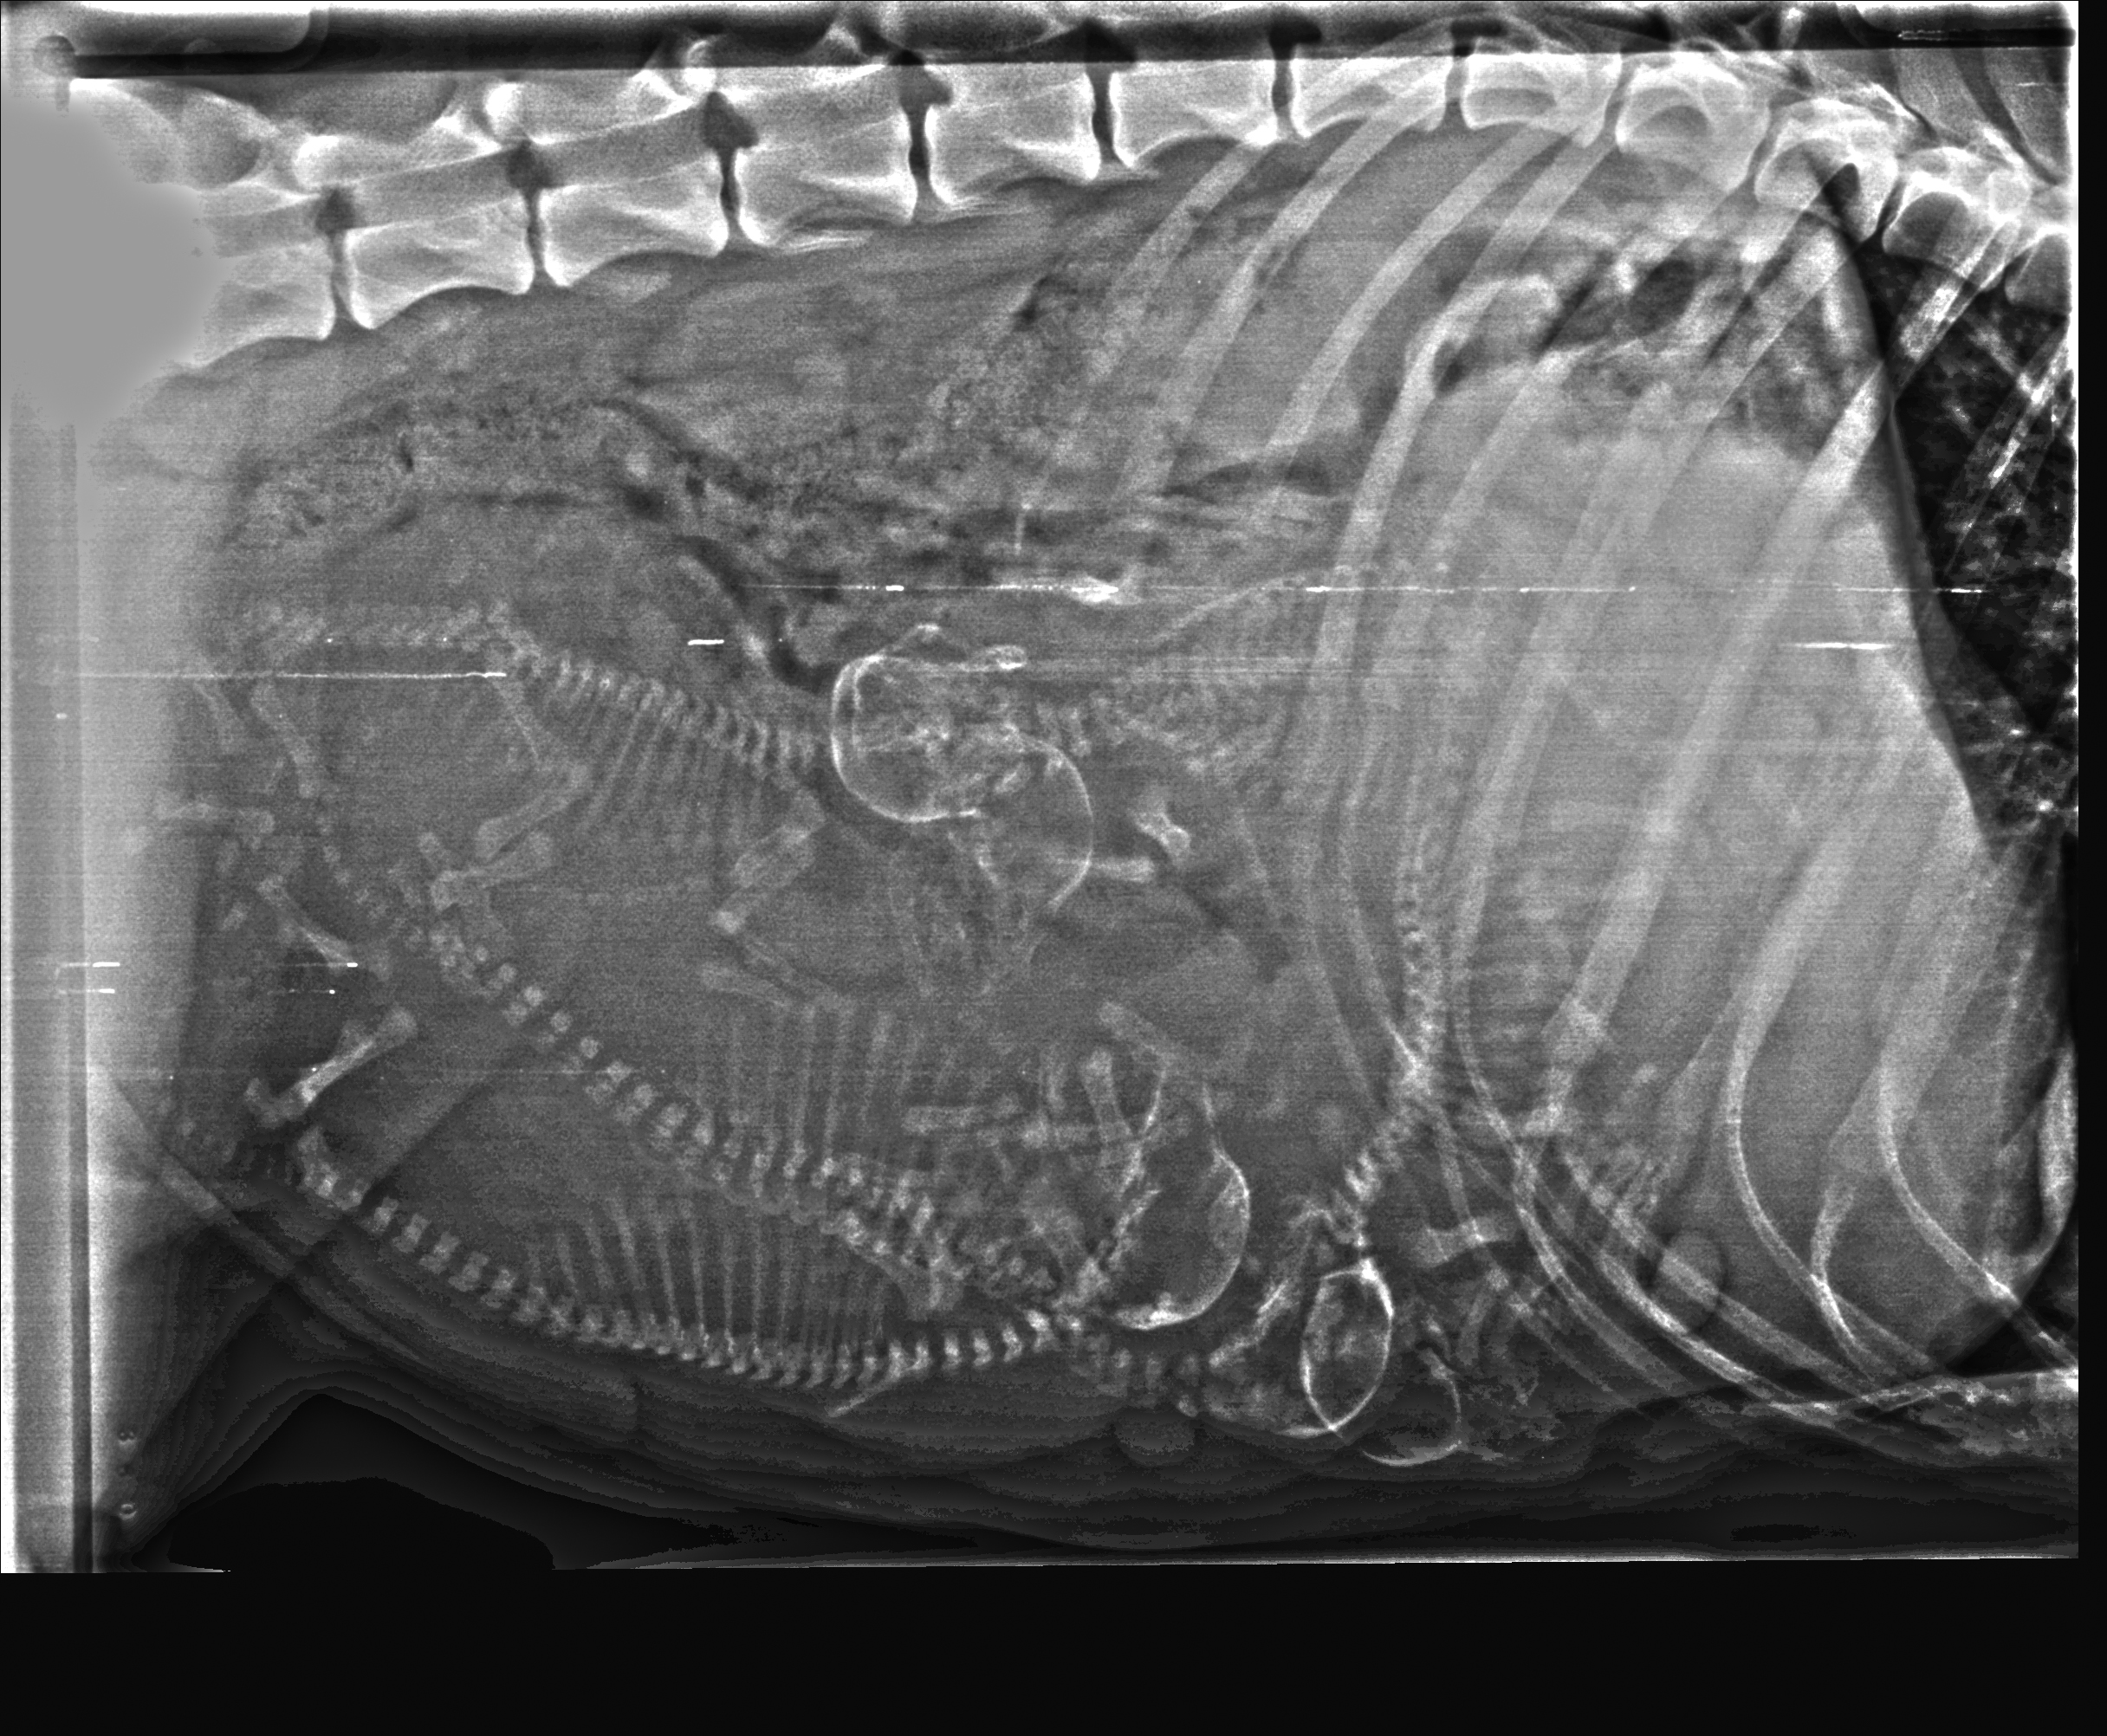

Hvor mange ser du?

Hei! Da har vi vært inne til røntgen av magen til Izel. Hvor mange teller du? Vi så hvertfall 5 hos veterinær. Legger ved både redigert bilde så det skal være enklere å telle i tillegg til original. Trykk på bildene for å se det i større format.